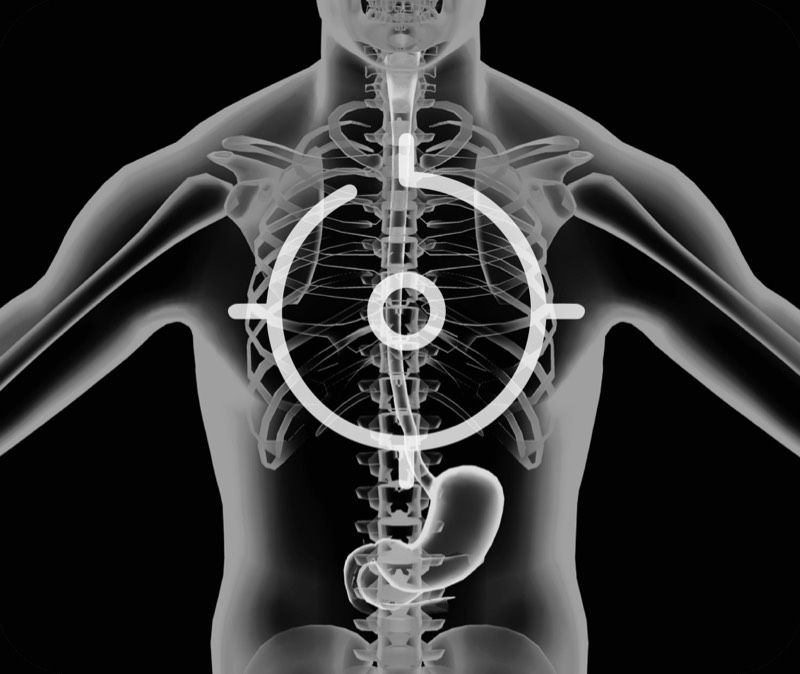

卓越的宽频设计,满足医生探查不同深度的组织和器官